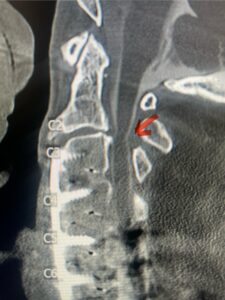

A 37-year-old male police officer complained of a one-month history of difficulty with his balance and leg weakness. He complained of achiness in his legs. He also complained of bilateral arm weakness and numbness of his hands. He was also having difficulty writing due to the weakness. Patient had an MRI of the cervical spine which demonstrated a disc/osteophyte at C56 causing spinal cord compression and concurrent myelomalacia (Fig. 3). Patient underwent an anterior cervical discectomy with a cage and plate (Fig. 4). He tolerated the procedure well with improved numbness and weakness. This is a young person with fairly extensive myelomalacia and a fairly rapid development of symptoms. For this it was felt surgery was indicated. How he will do will depend on how much of his symptoms was caused by the compressive component or intrinsic damage to the spinal cord. As a rule, patients generally improve to some extent quickly; but their recovery of their spinal cord function can sometimes take up to 2 years to realize the extent of their improvement. Patients have to be patient with themselves in terms of their expected recovery.

Fig. 3: Sagittal T2-weighted cervical MRI demonstrating a significant disc osteophyte complex causing spinal cord compression at C 5 6 with extensive myelomalacia (red arrow)

Fig 4: Sagittal T2-weighted cervical MRI demonstrating a significant disc osteophyte complex causing spinal cord compression at C 5 6 with extensive myelomalacia (red arrow)